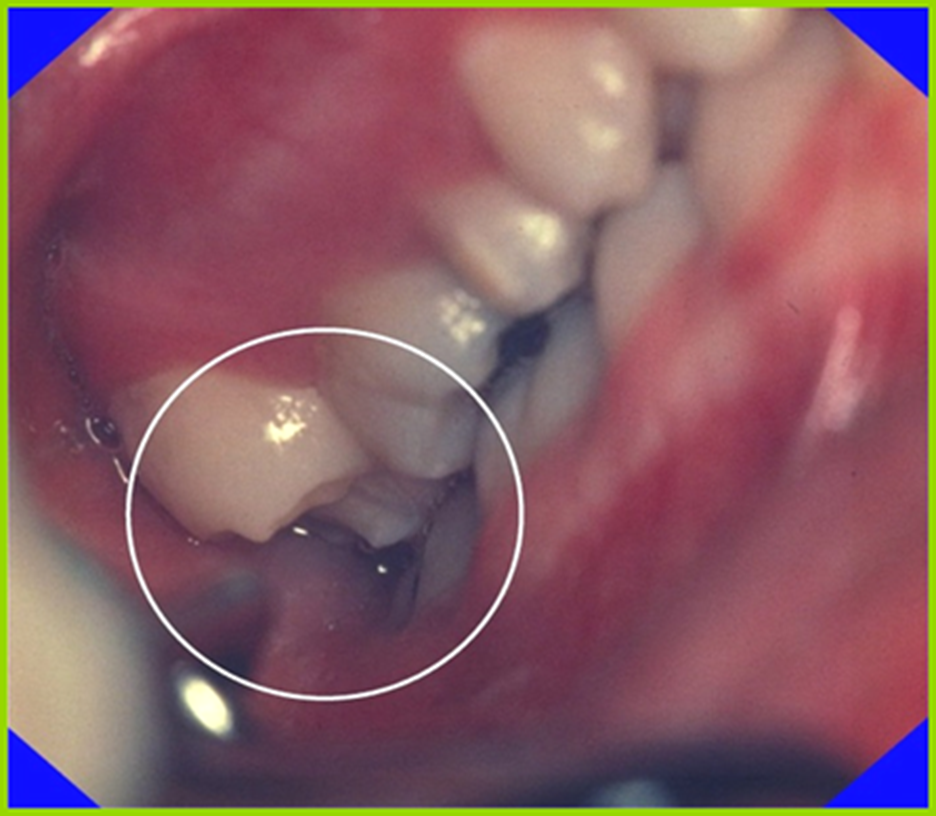

Om enstaka tänder erupterar buckalt eller lingualt på grund av platsbrist, så kan saxbitning uppkomma. Kliniskt kan detta ses framför allt på permanenta första premolarer och andra molarer. (Bild 3)